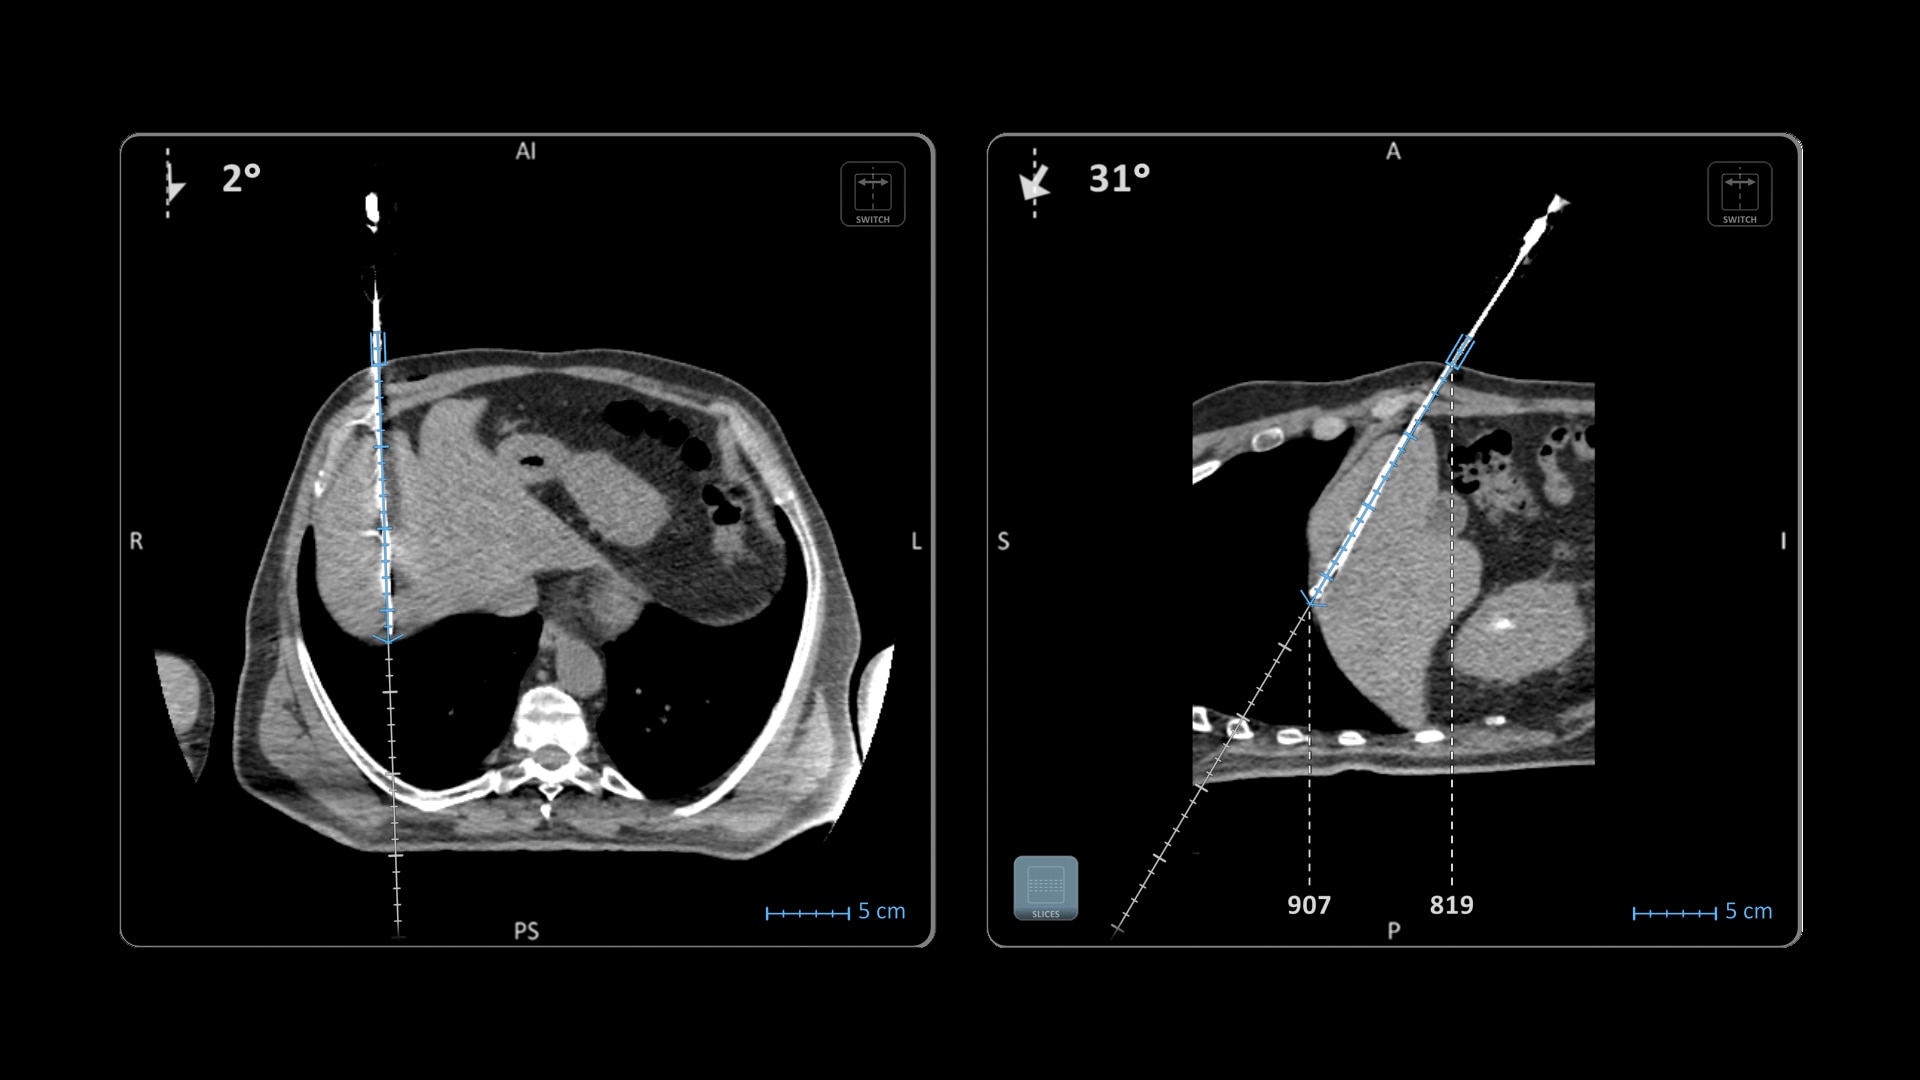

Versatility

Ideal to use with various percutaneous interventions² with various complexity